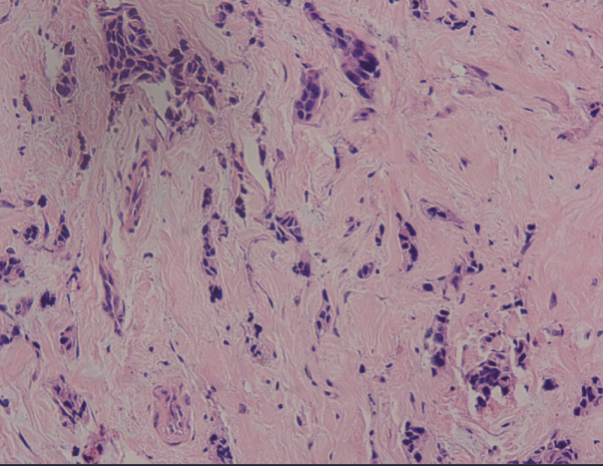

HE染色